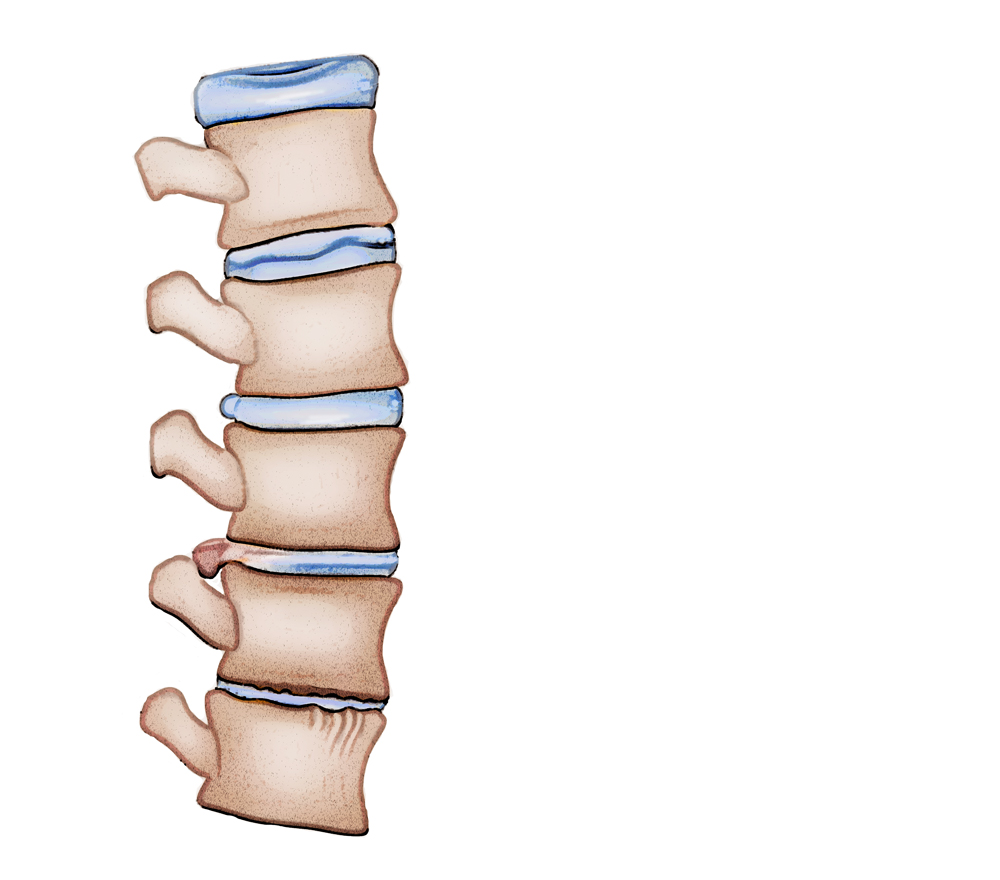

pictures of bulging discs in lower back

Bulging disc-Lower back pain

Bulging Discs And How You Can Slow Them Down